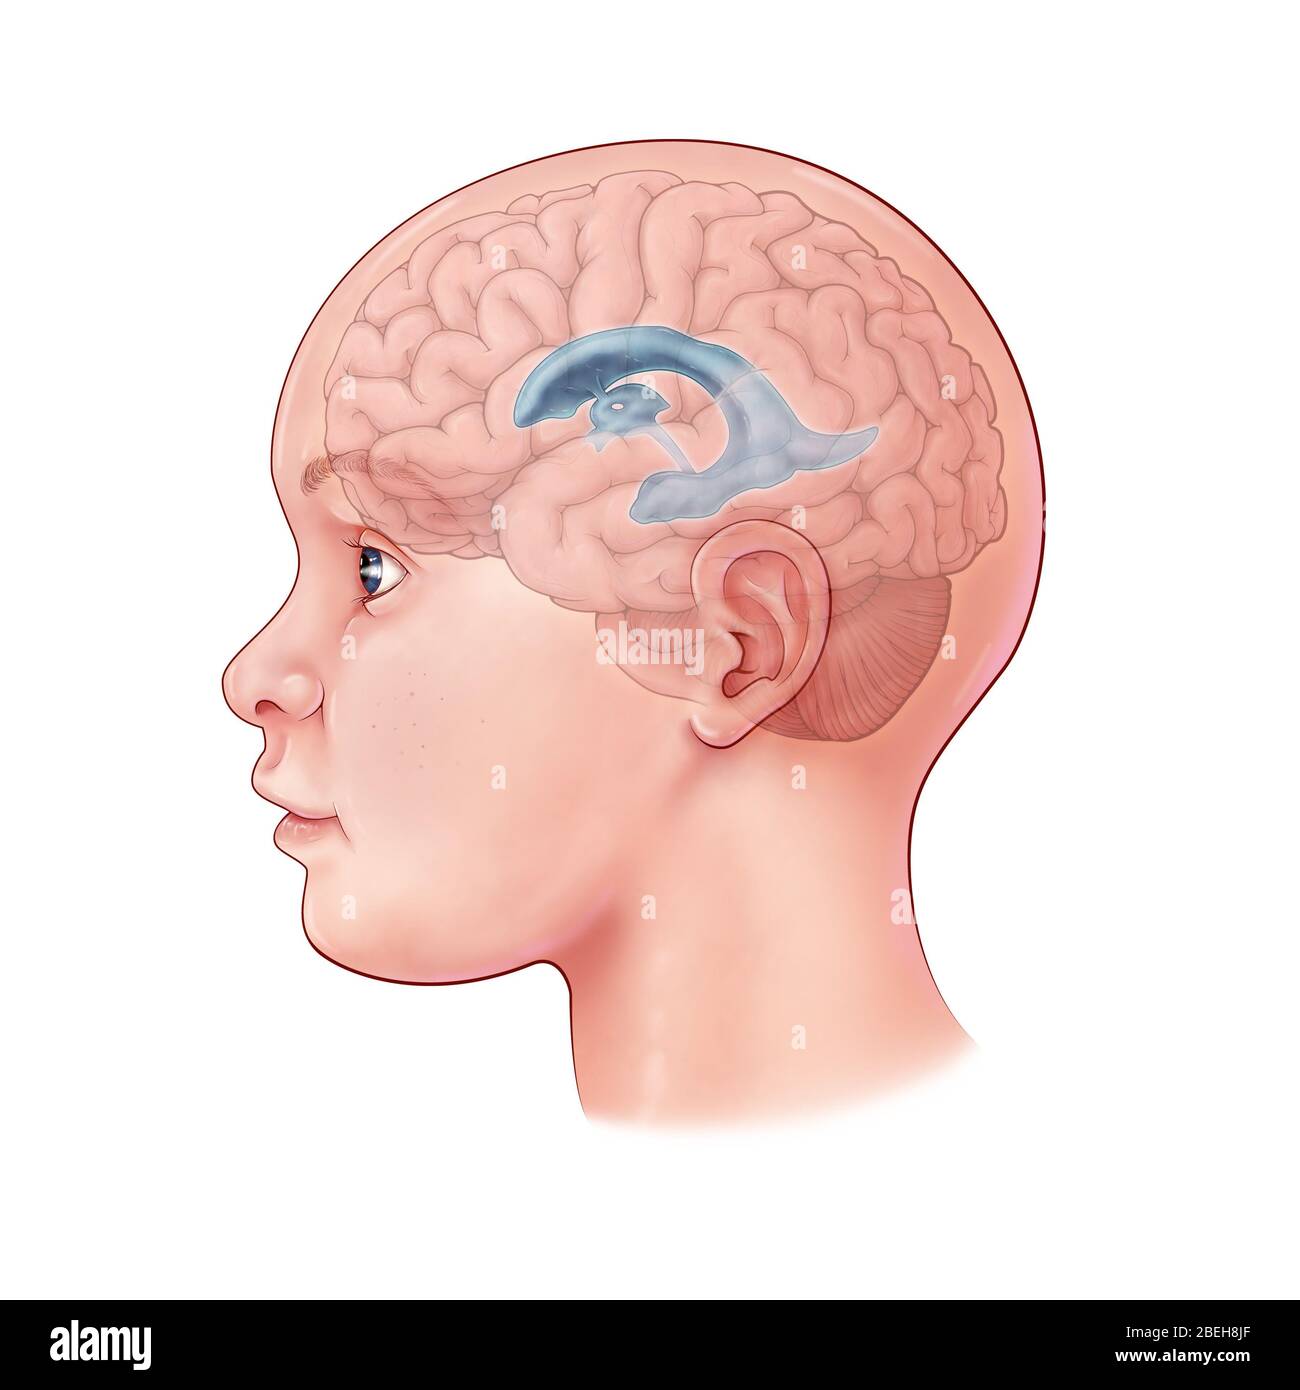

RF3CN8WHW–Darstellung der vergrößerten lateralen und dritten Ventrikel des Gehirns (Hydrozephalus), hervorgerufen durch einen Hirntumor, der den Aquädukt des Gehirns komprimiert.

RF3CN8WHP–Illustration des vergrößerten lateralen und dritten Ventrikels des Gehirns (Hydrozephalus), hervorgerufen durch einen Hirntumor, der den Aquädukt des Gehirns komprimiert.

RF3CPM9D2–Darstellung der vergrößerten lateralen und dritten Ventrikel des Gehirns (Hydrozephalus), hervorgerufen durch einen Hirntumor, der den Aquädukt des Gehirns komprimiert.

RF3CPM9D7–Darstellung der vergrößerten lateralen und dritten Ventrikel des Gehirns (Hydrozephalus), hervorgerufen durch einen Hirntumor, der den Aquädukt des Gehirns komprimiert.

RF3CPM9DA–Darstellung der vergrößerten lateralen und dritten Ventrikel des Gehirns (Hydrozephalus), hervorgerufen durch einen Hirntumor, der den Aquädukt des Gehirns komprimiert.

RF3CPM9D6–Darstellung der vergrößerten lateralen und dritten Ventrikel des Gehirns (Hydrozephalus), hervorgerufen durch einen Hirntumor, der den Aquädukt des Gehirns komprimiert.